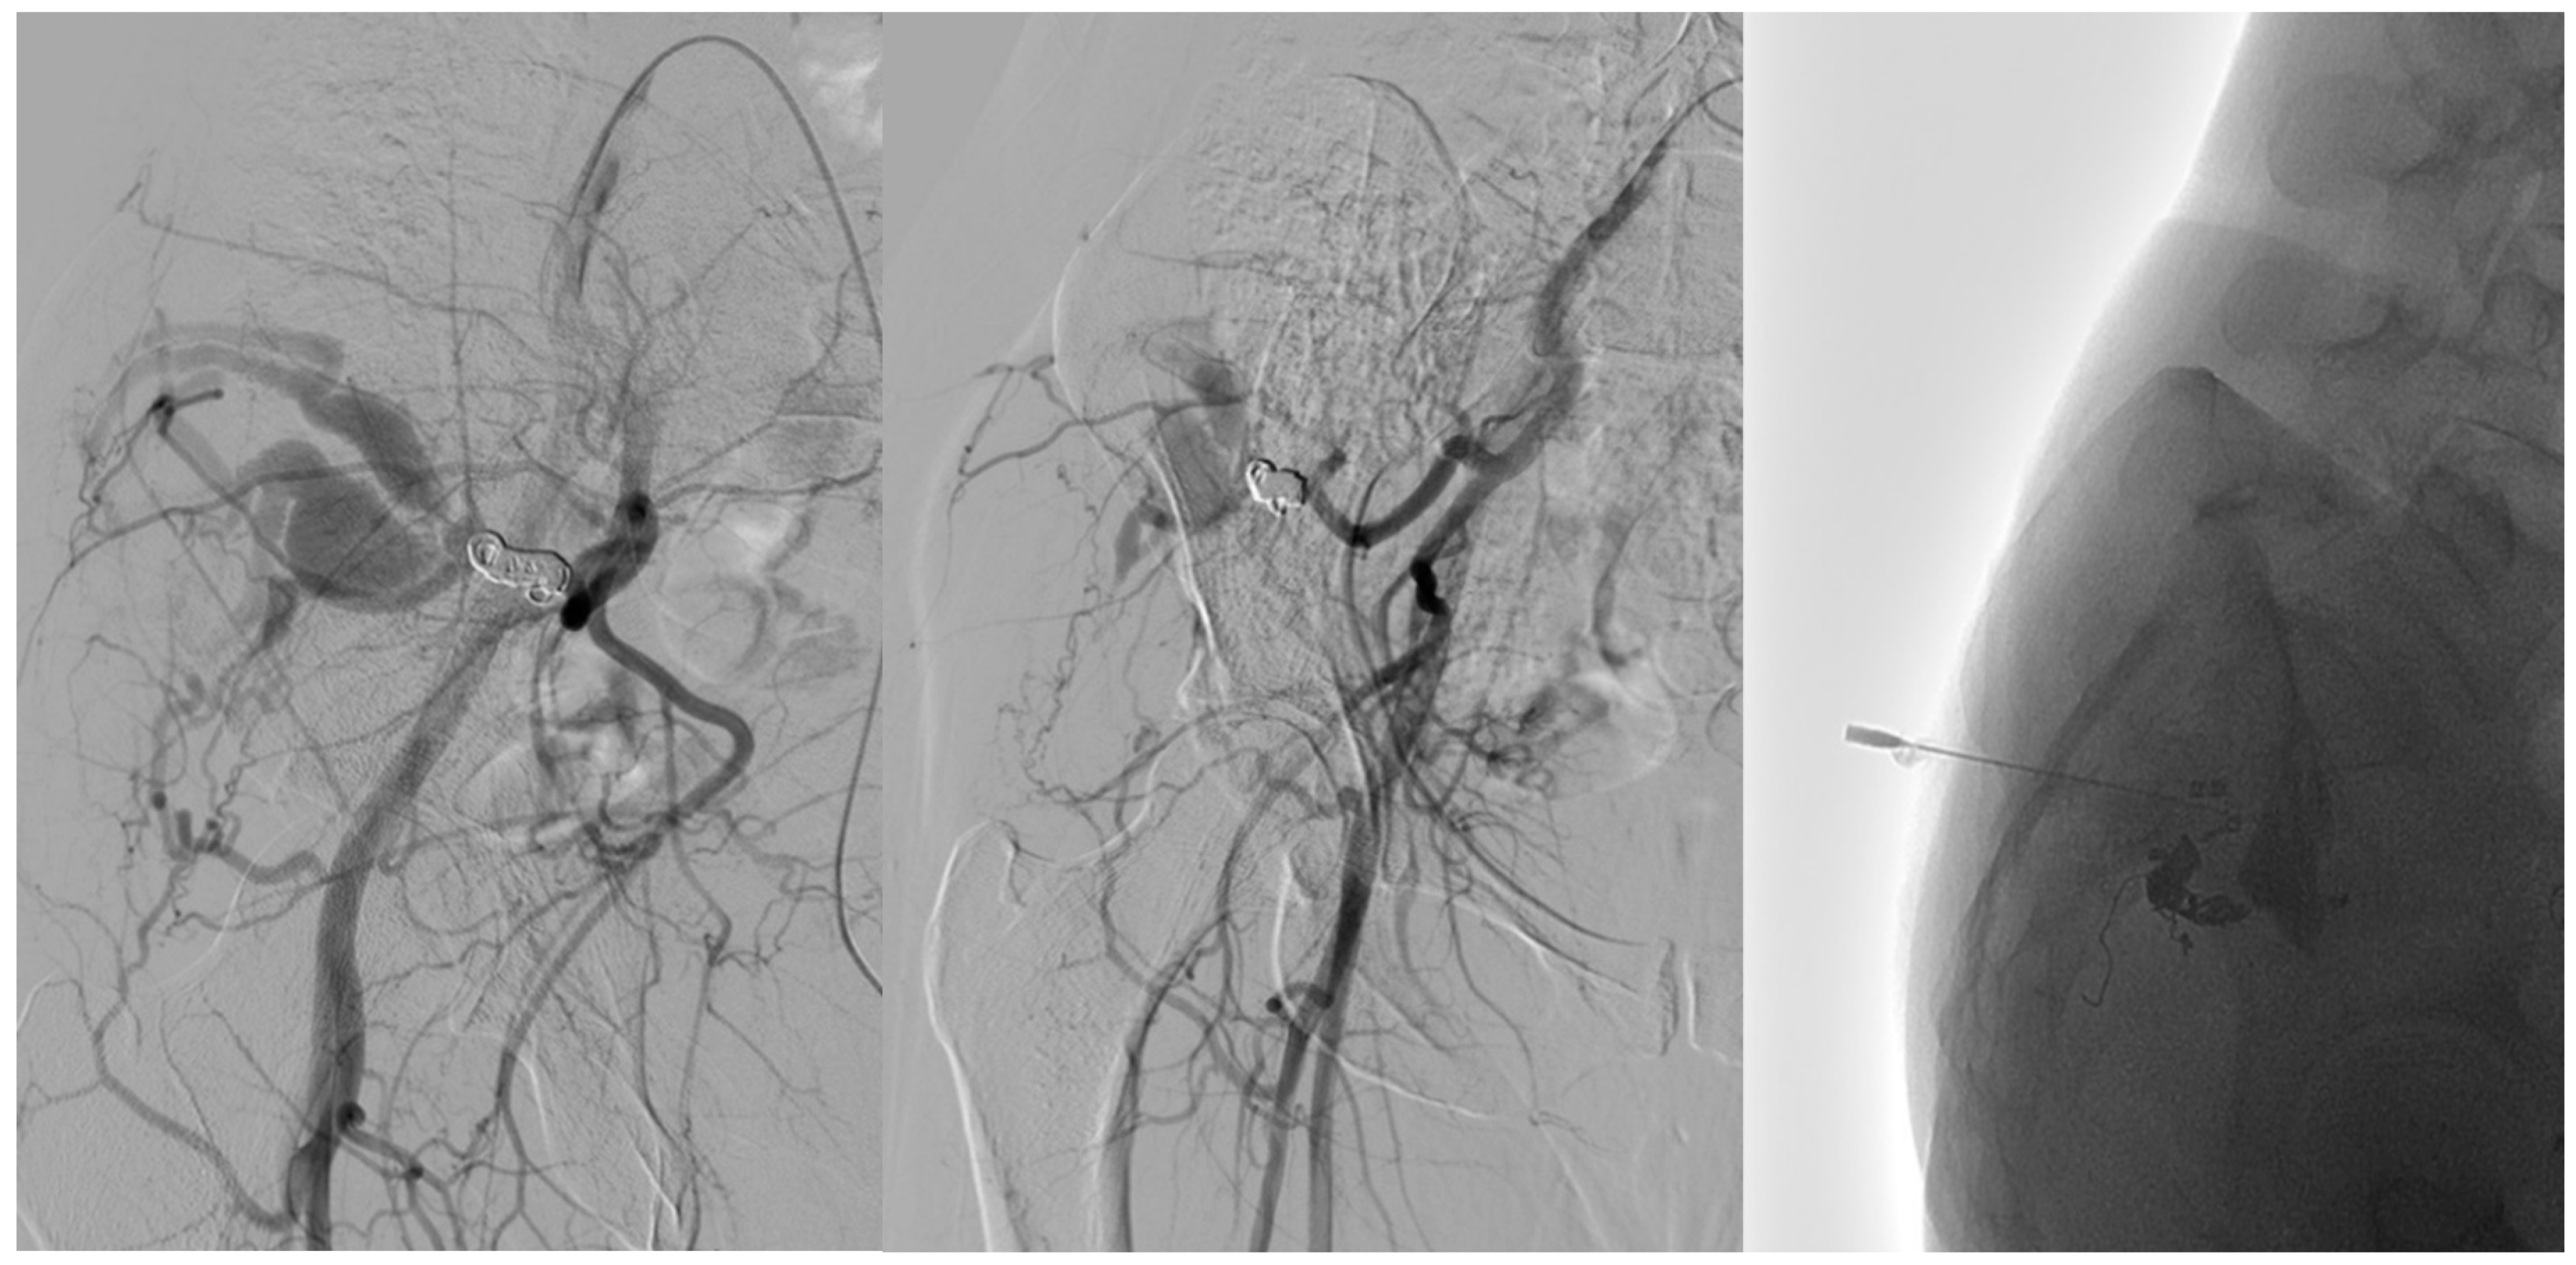

- Arterial embolization was preferred in lesions with limited and accessible feeders.

- Venous embolization was favored when the dominant outflow vein (DOV) was accessible and formed the site of arteriovenous shunting.

- Combined arterial and venous embolization was used in complex lesions with multilevel shunting, high-flow recurrence, or partial response to single-route embolization.